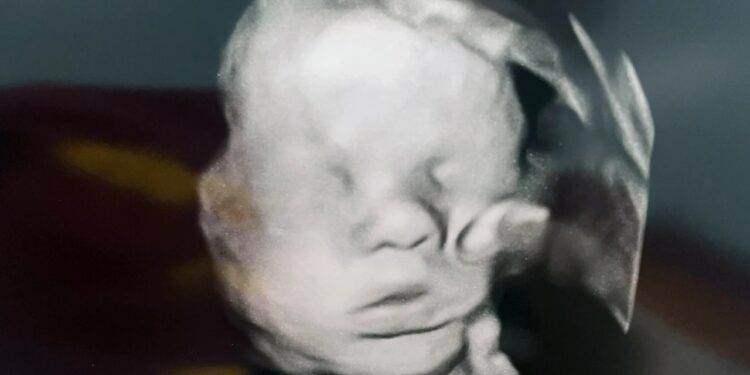

Κατά τον υπερηχογραφικό έλεγχο στις 32 εβδομάδες κύησης, η Αμάντα Φόστερ, 33 ετών, αντίκρισε κάτι απροσδόκητο: μια μεγάλη παλάμη που φαίνεται να αγγίζει απαλά το κεφάλι του αγοριού που κυοφορεί. Όπως λέει, δεν ήταν ένα τυχαίο σημάδι:

Η στιγμή για το υπερηχογράφημα ήταν ιδιαίτερη: πήγε μαζί με τη μικρότερη κόρη της, τη Μπέιλι. Ήταν εκείνη που εντόπισε πρώτη το μεγάλο χέρι στην εικόνα, το οποίο ακουμπά απαλά το πρόσωπο του αγέννητου μωρού.